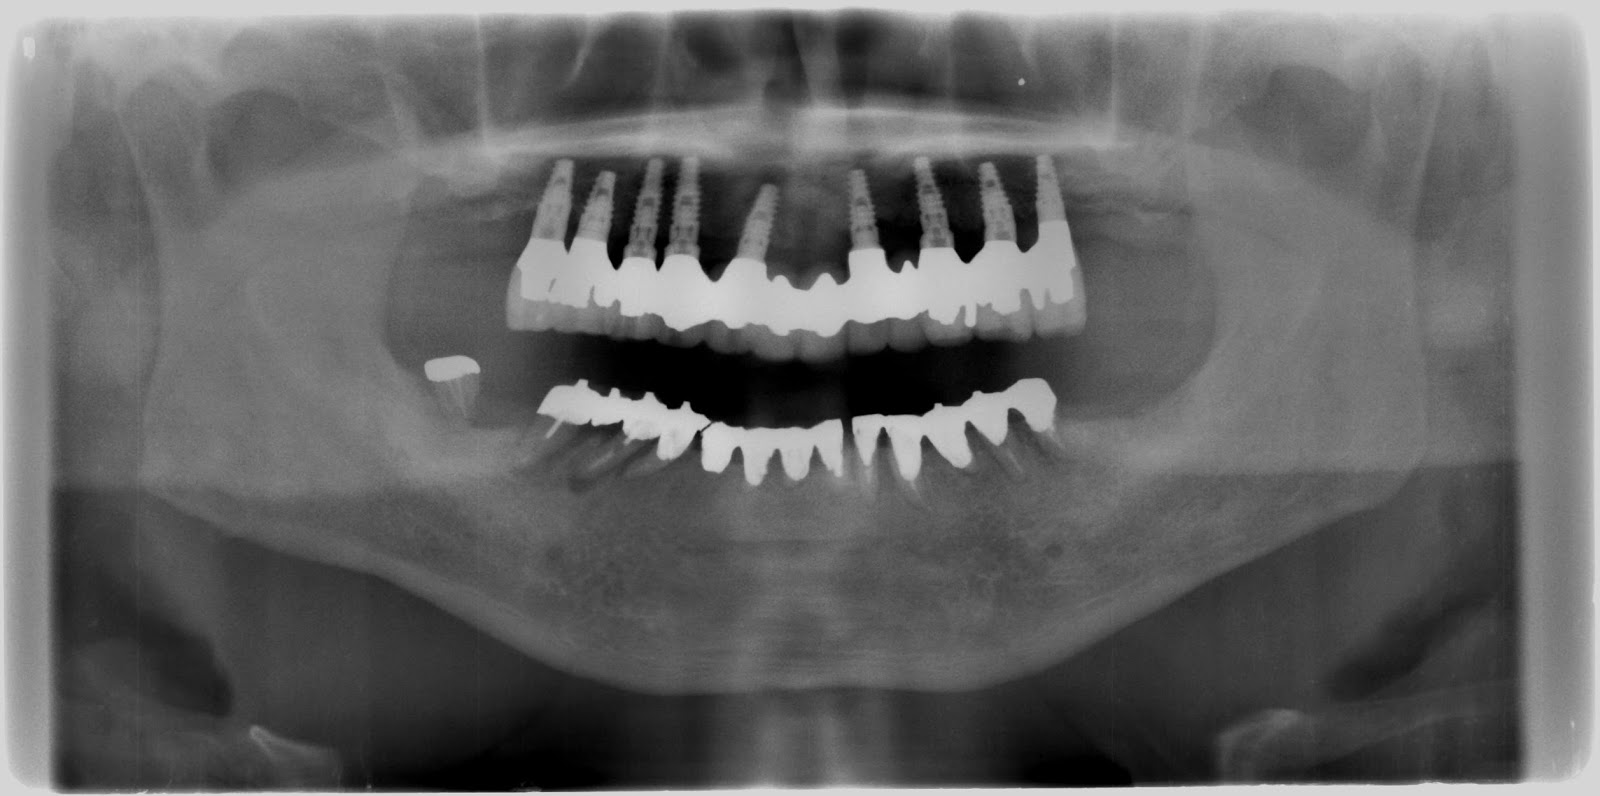

昔はこんな感じ。北陸でもつい最近までこういうオペを普通にしていたようです。今は少くなっているとは思いますが。